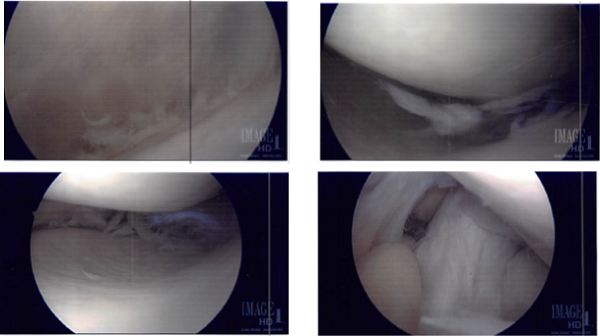

The tourniquet was inflated. Lateral entry portal was made and the scope was entered. Osteochondral OA grade 3 to grade 4 damage was found on the lateral inferior patella. Lot of debris was found in the knee as in the suprapatellar pouch and medial gutter.

The knee scope was moved to the medial compartment where a lot of debris as well as medial meniscus tear could be seen. medial entry portal was made. A probe was entered and meniscal tear were examined and pictures! was taken.

A shaver was inserted to clean off the debris as well as margins on the medial meniscus. The final balancing of the medial meniscus was performed. The lesion was also debrided. Microfracture of patellar osteochondral defect was done using pigtail punches and subchondral fat globules could be seen from the microfracture site.

Intraoperative Images from start to final process